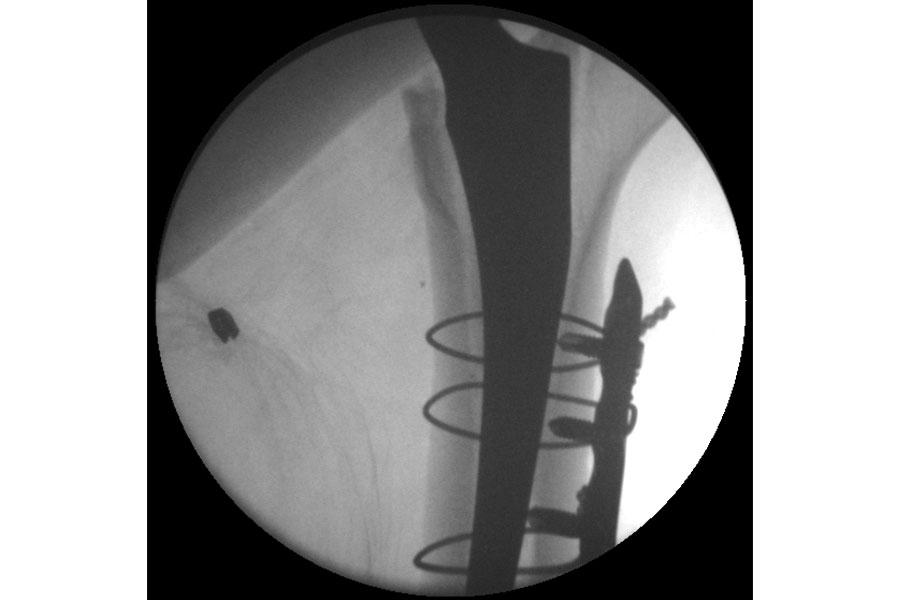

Trauma

Case 1